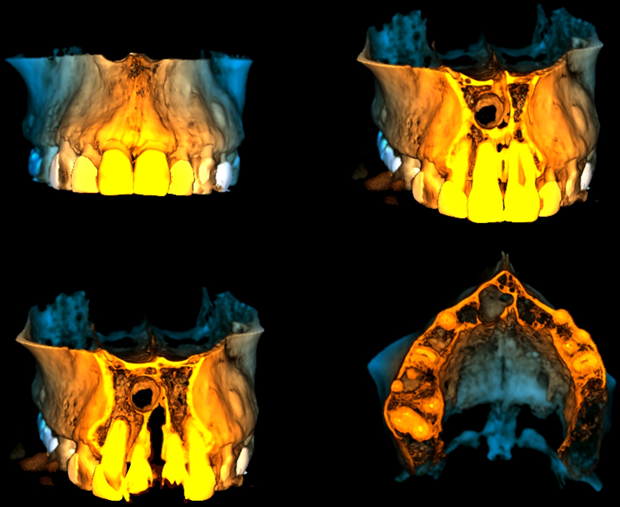

En las reconstrucciones 3D se representa Quiste Nasopalatino. (Figura 4).

RECONSTRUCCIÓN 3D

CASO 336 - RECONSTRUCCION 3D - IDM

• Quiste Nasopalatino.